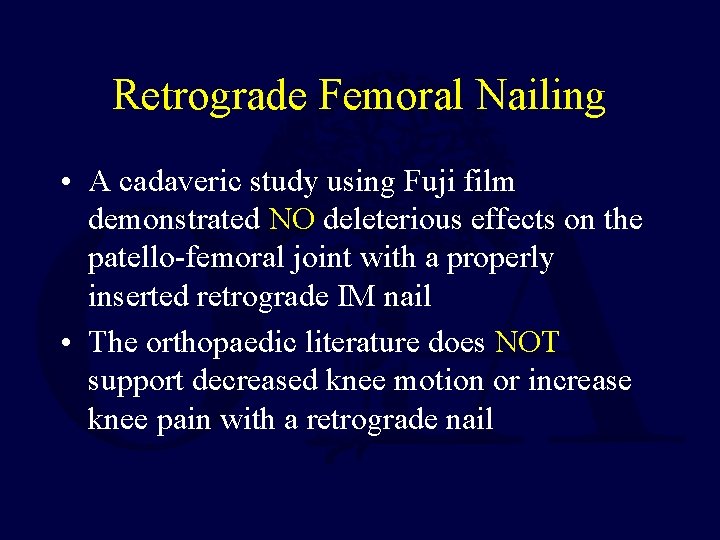

Retrograde Femoral Nailing • A cadaveric study using Fuji film demonstrated NO deleterious effects on the patello-femoral joint with a properly inserted retrograde IM nail • The orthopaedic literature does NOT support decreased knee motion or increase knee pain with a retrograde nail

Femur Fracture Management • Retrograde Nailing – Union rates lower with unreamed nails – Higher dynamization with non canal sized nails – Better union rates equal to antegrade with reamed canal sized nails • Moed JBJS 1995, J Orthop Trauma 1998 • Ostrum J Orthop Trauma 1998, 2000 – Advantages for ipsilateral acetabulum or femoral neck and shaft fracture, floating knees, obese patients, supracondylar fractures including those around total knee replacements